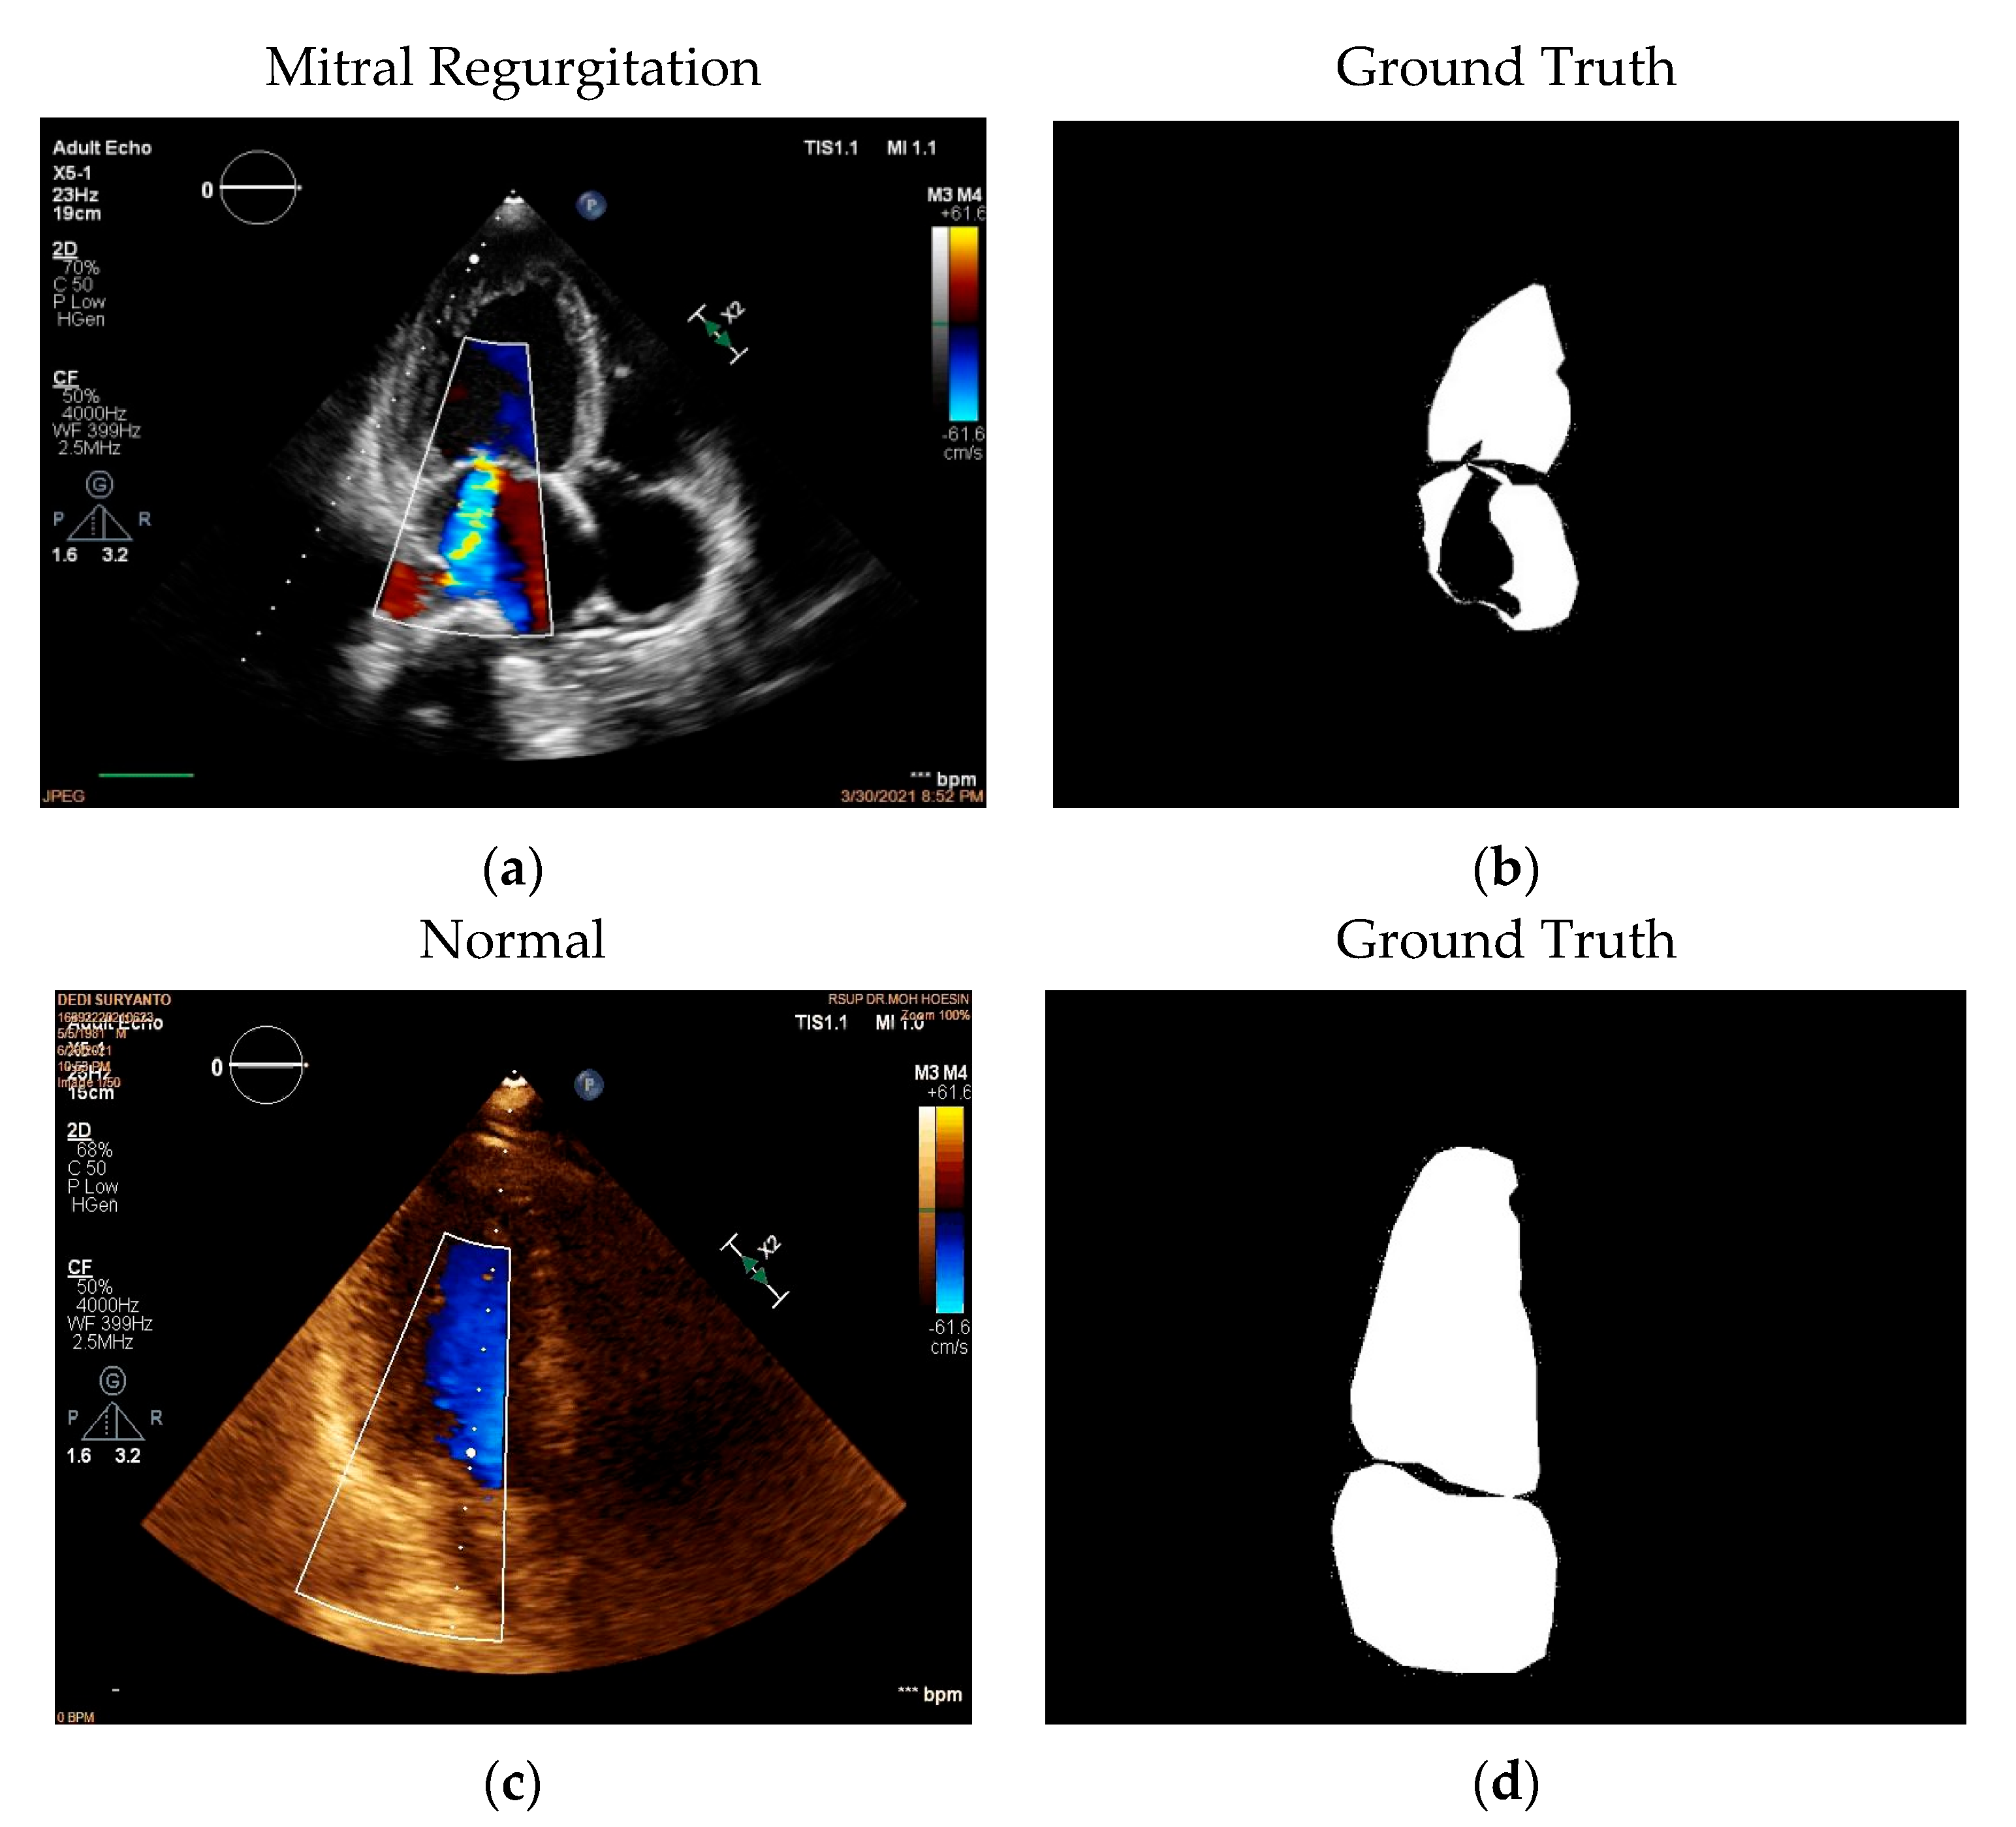

2.1. Data Acquisition

2.2. Data Pre-Processing